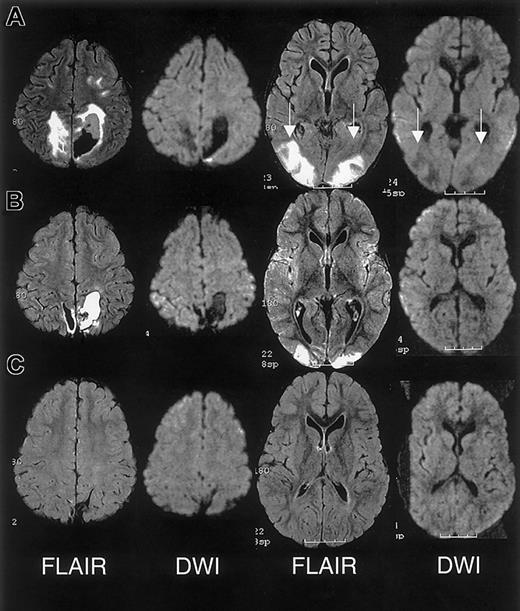

RPLS is difficult to distinguish from acute cerebral infarcts clinically and radiographically. The distinction is important because cerebral infarction implies irreversible damage and warrants blood transfusion therapy for an indefinite period. Conversely, RPLS is potentially reversible but may require judicious hypertensive management. In this case series, 2 patients were originally diagnosed as having cerebral infarcts according to the clinical reading of the MRI, one of whom was subsequently determined to have RPLS and the other with cerebral hemorrhage. Appropriate MRI techniques and interpretation play a key role in differentiating RPLS from cerebral infarct (Figure 4). Both RPLS and cerebral infarct present with T2-weighted hyperintensities. DWIs typically show hyperintense signal in cerebral infarcts, whereas DWIs in RPLS are ambiguous because of T2 shine-through effects.8 14 Producing images of the diffusion coefficient eliminates this ambiguity.

Characterization of T2-weighted hyperintensities on MRI of the brain distinguishing cerebral infarct from reversible posterior leukoencephalopathy syndrome (RPLS).

DWI indicates diffusion weighted image; DC, diffusion coefficient.

The initial clinical reading of the MRI, 1 day following endotracheal extubation, was bilateral ischemic infarcts and biparietal hemorrhages. The subsequent research reading of the initial MRI and follow-up MRI at 1 month and 15 months following discharge revealed findings consistent with RPLS complicated by hemorrhage; there was no evidence of infarction (Figure 3).

MRI findings for case 3.

(A) Extensive areas of FLAIR T2-weighted signal hyperintensity in the subcortical white matter and overlying gray matter of the posterior, frontal, and occipital lobes. Parenchymal hemorrhage was seen in the high parietal region predominantly on the patients's left. (B-C) Follow-up MRI scan 1 month and 15 months following discharge showed progressive evolution and resolution of the T2 signal hyperintensities with residual encephalomalacia in the left parietal region. These findings were consistent with reversible posterior leukoencephalopathy complicated by hemorrhage; there was no evidence of infarction.